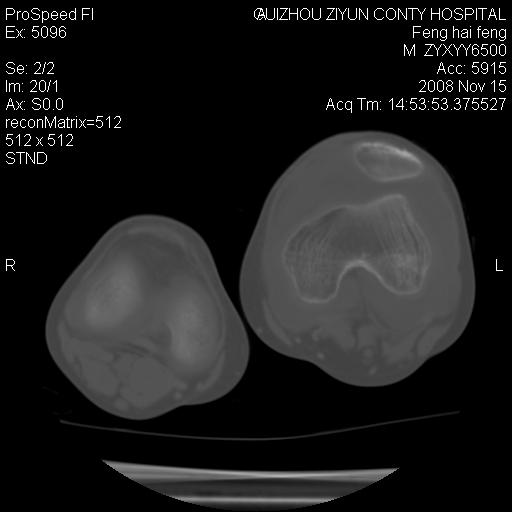

标题: CT16656:M 14Y 左膝关节肿胀一年余。其余病史不详。 [打印本页]

标题: CT16656:M 14Y 左膝关节肿胀一年余。其余病史不详。

考虑左侧髌骨结核;左膝关节滑膜肿胀、增厚,关节囊积液。

左膝滑膜型关节结核可能性大!支持!滑膜型关节结核主要ct表现:关节囊肿胀,积液,关节面见小破坏灶,并见点状死骨!

好大的左腿!考虑左侧髌骨结核,左膝关节滑膜肿胀、增厚,关节囊积液。

左侧髌骨结核;左膝关节滑膜肿胀、增厚,关节囊积液